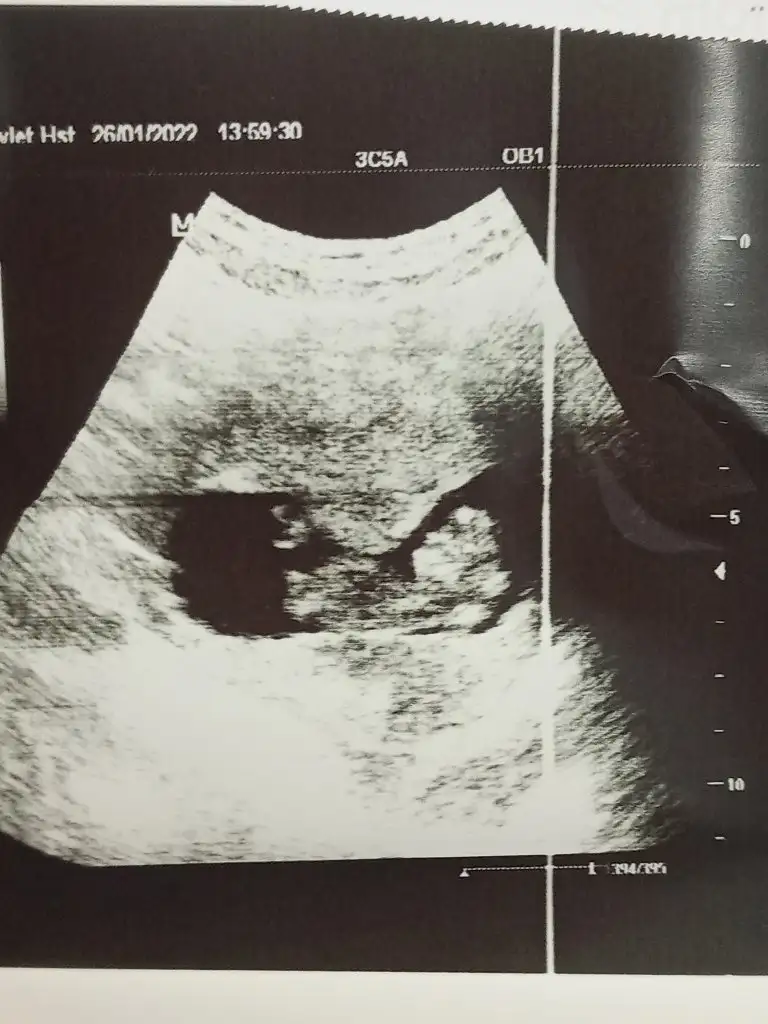

Bana da bakabilir mısınız acaba. Vajinal ultrason

• 16431943366089167991943681651978.webp

16431943366089167991943681651978.webp

31,9 KB · Görüntüleme: 66